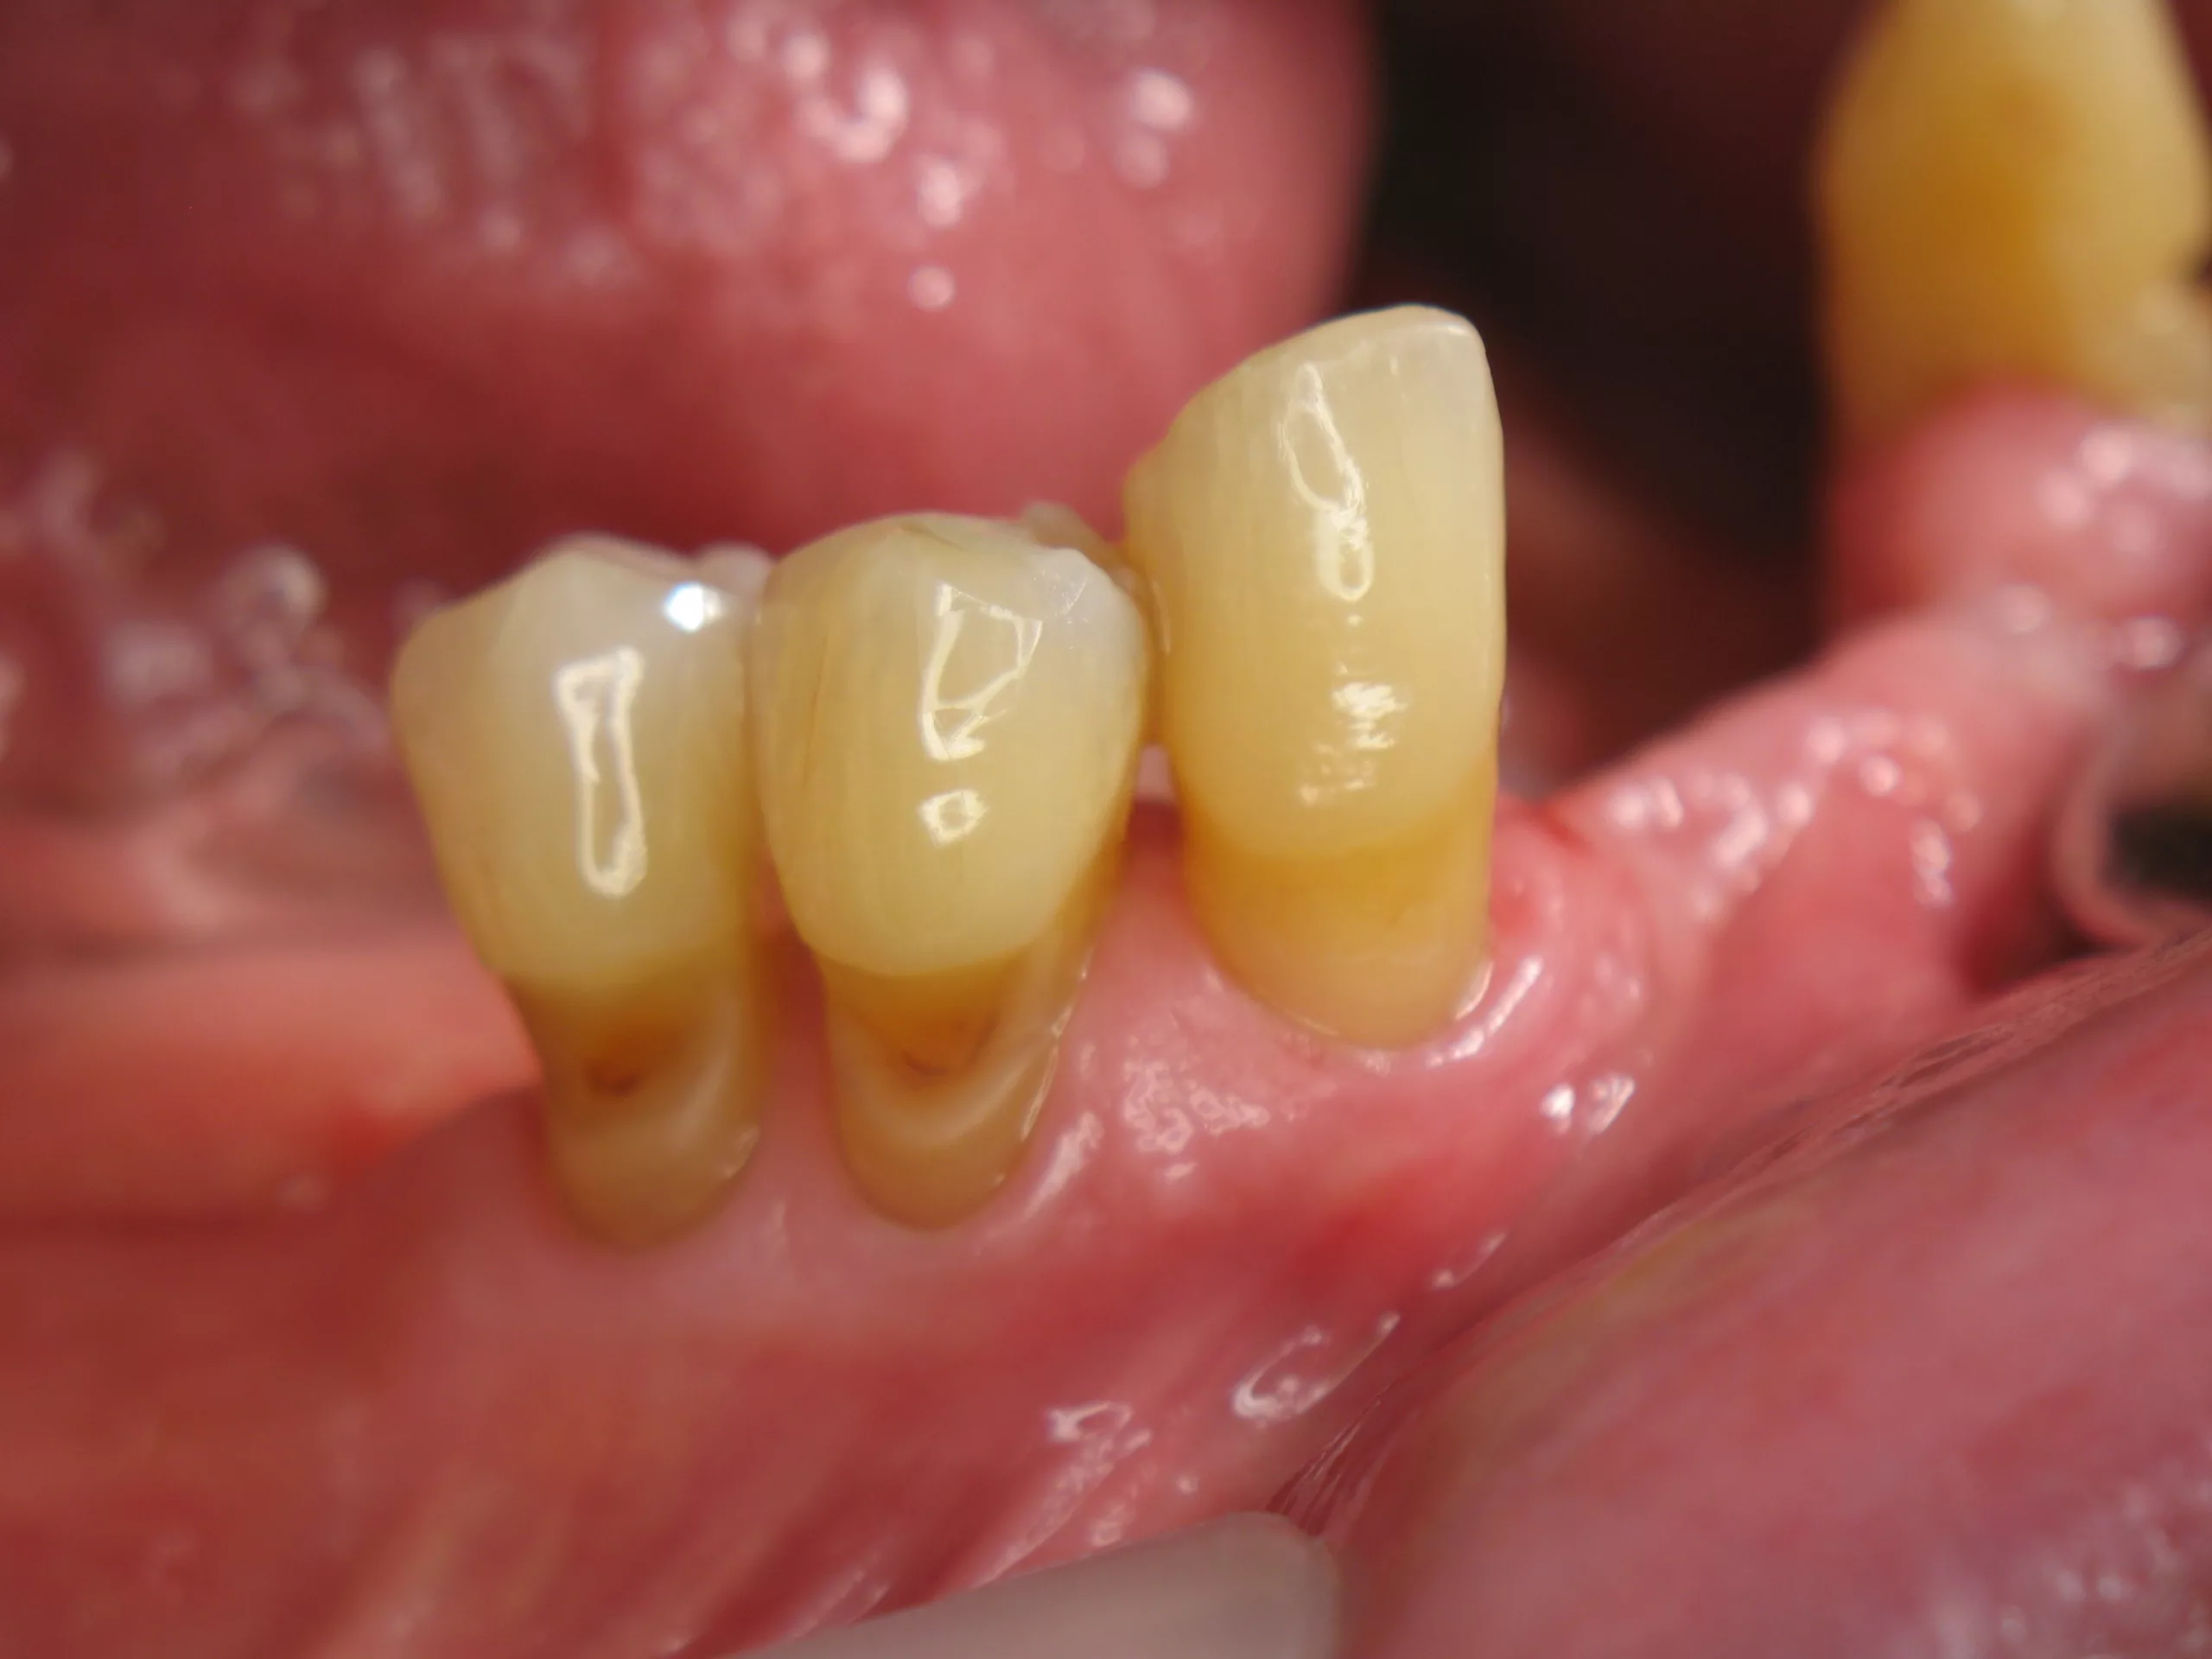

Klinisch war eine Stabilisierung der kariösen Läsionen sichtbar (Abb. 6). Angesichts der generell schwierigen Mundhygienesituation bei Senioren sowie ihrem höheren Risiko für freiliegende Zahnhälse und Karies, kann eine Zahnpaste mit erhöhter Fluoridkonzentration wie Duraphat® Fluorid 5mg/g als Mittel der Wahl in der Seniorenzahnmedizin gelten.